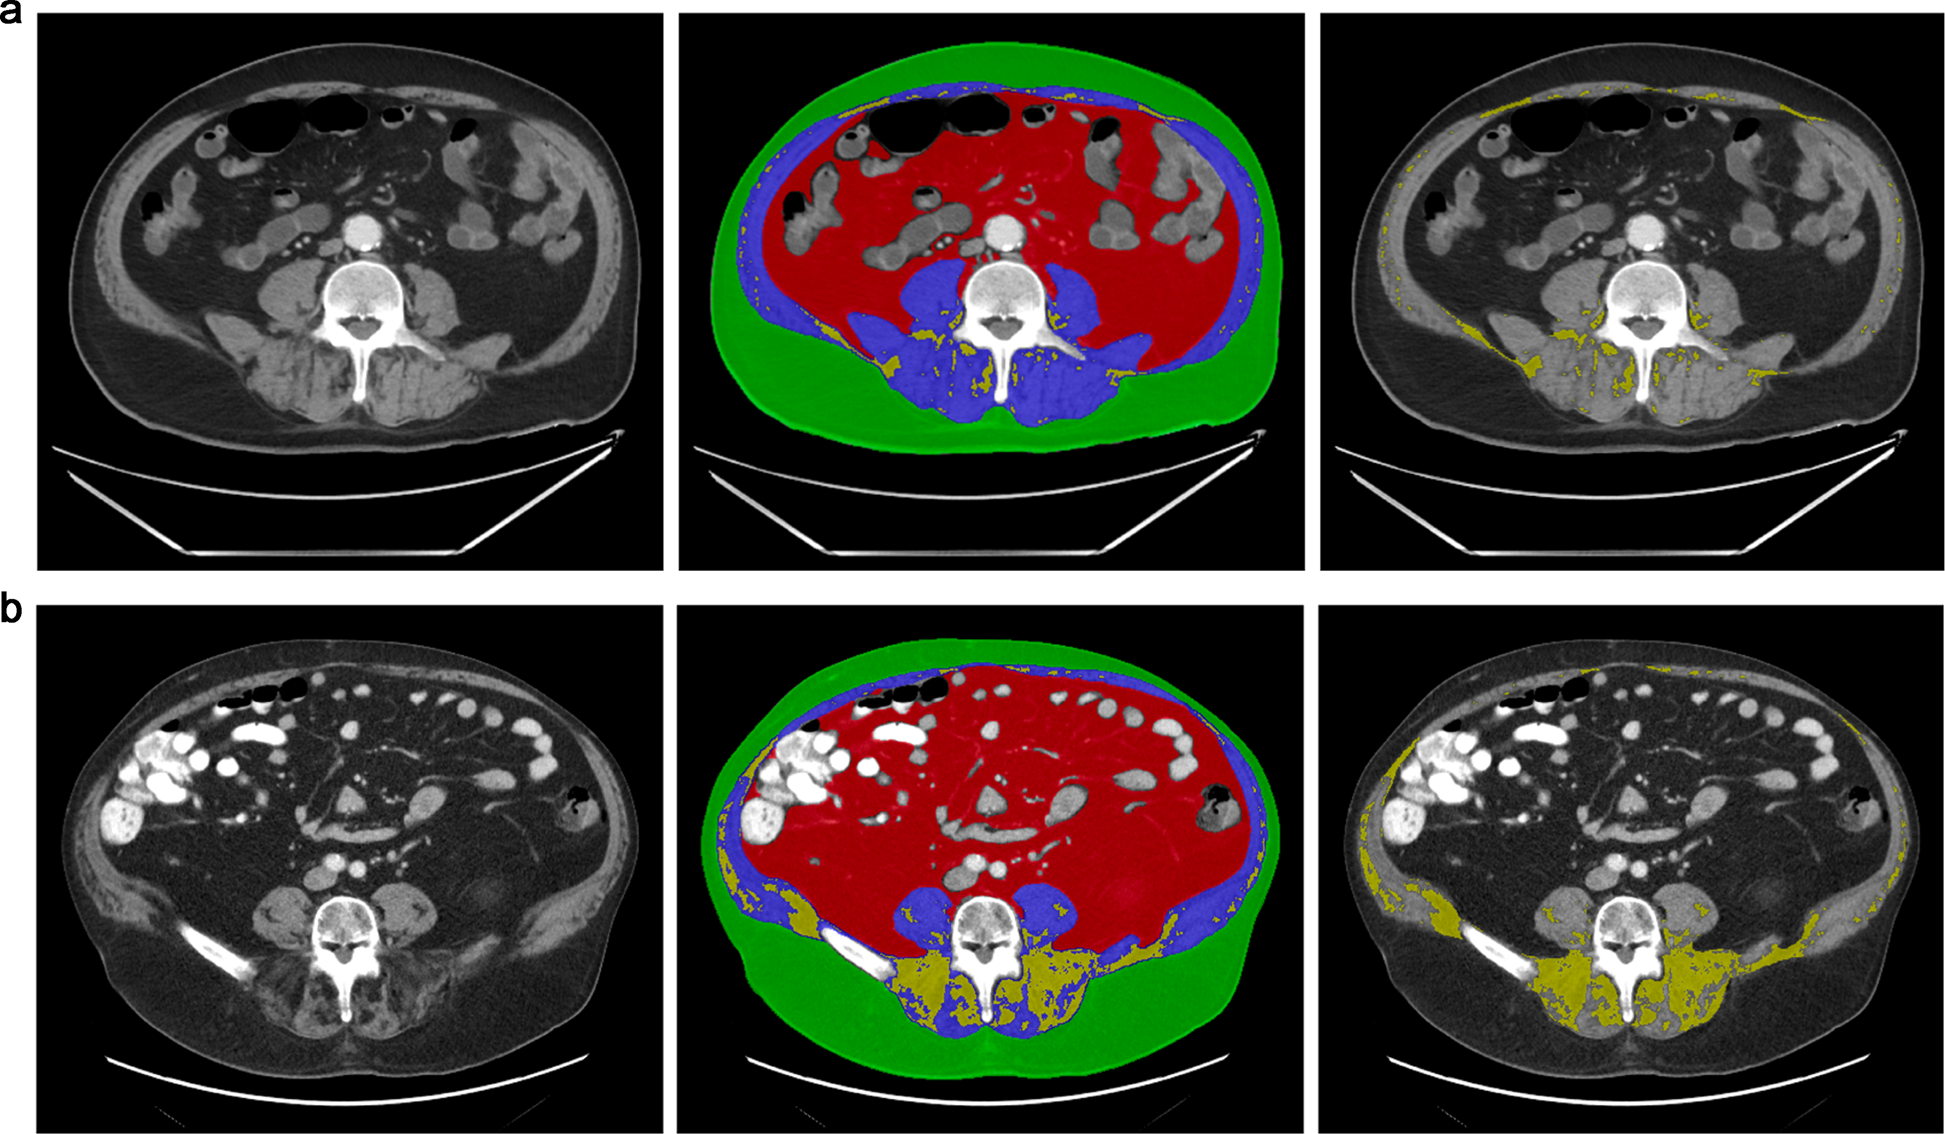

Fig. 2: Body composition assessment in patients with COVID-19.

a 73-year-old woman with obesity (BMI 33.4 kg/m2) admitted with COVID-19, who was alive after the follow-up period. Subcutaneous adipose tissue (SAT) cross-sectional area (CSA) 155.1 cm2, visceral adipose tissue (VAT) CSA 161.2 cm2, VAT/SAT ratio 1.04, muscle CSA 124.5 cm2, intermuscular adipose tissue (IMAT) CSA 15.3 cm2. b 76-year-old woman, BMI 35.4 kg/m2, admitted for COVID-19 who died 8 days after hospital admission: SAT CSA 217.9 cm2, VAT CSA 417.7 cm2, VAT/SAT ratio 1.92, muscle CSA 119.2 cm2, IMAT CSA 66.4 cm2. Despite similar BMI, the patient who died had higher visceral adiposity and higher IMAT.